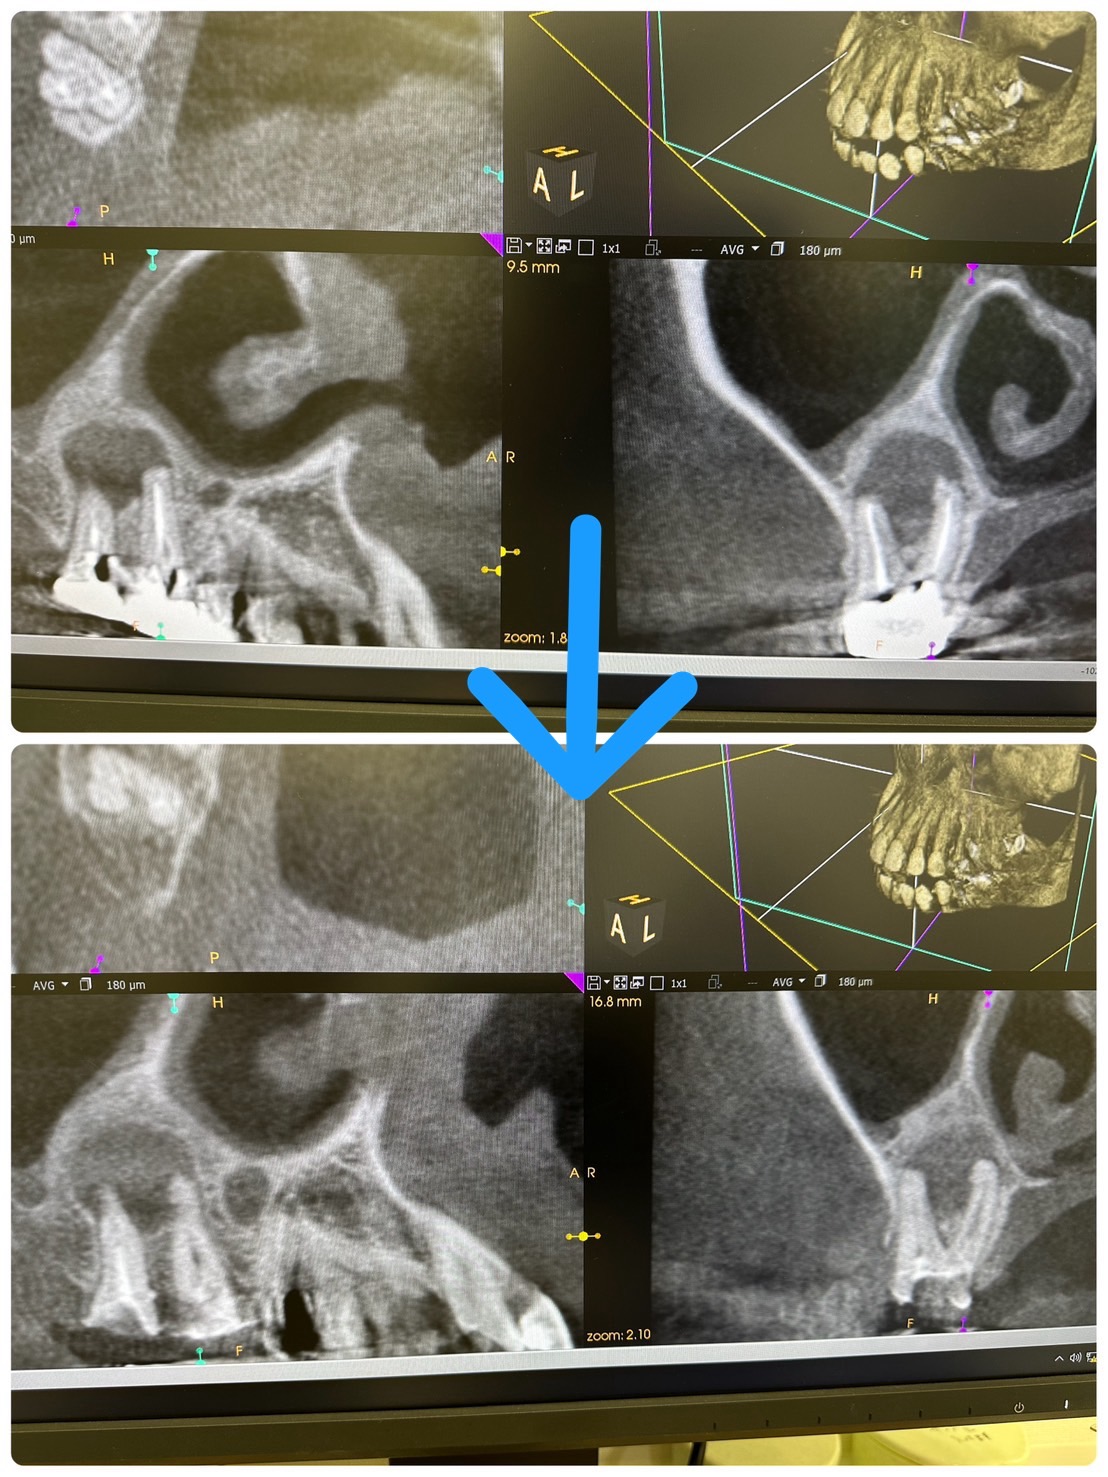

新大久保歯科医院